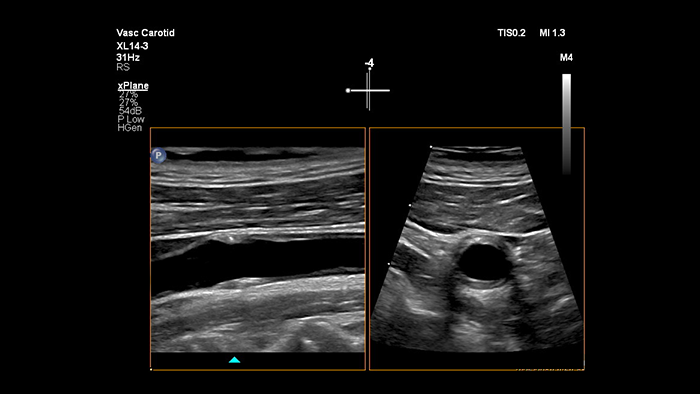

Il trasduttore XL14-3 xMatrix offre imaging xPlane che va oltre l'approccio convenzionale agli esami vascolari grazie a immagini in tempo reale acquisite contemporaneamente sul piano longitudinale e trasversale. Vantaggio principale: l'imaging xPlane elimina la necessità di ruotare il trasduttore per acquisire viste ortogonali. Con un semplice movimento della trackball è possibile svolgere una valutazione anatomica completa, risparmiando tempo durante l'esame.